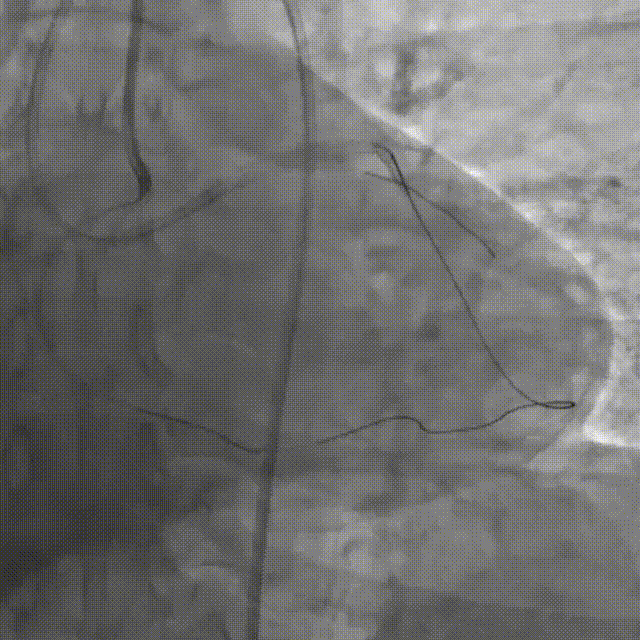

双侧造影明确LAD开口位置和临近血管关系。

Corsair135辅助下先后尝试使用P200/G3导丝未能突破近端纤维帽,最终CP12突破后进入血管结构内,同时进行多角度确认。

尝试调整导丝重回真腔未成功,直接使用XTA导丝knuckle。

跟进corsair并交换LP球囊后,先后尝试G3/CP12/8-20等导丝穿刺均失败。